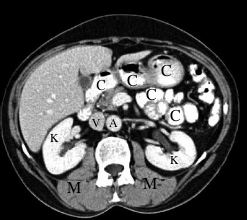

Later after IV contrast injection-aorta (A) and inferior vena cava (V) are now similar in color, both lighter than muscle (M). Kidneys (K) are uniformly white. The amount of time it takes for IV contrast to circulate around from arteries to veins depends on cardiac function. Note that there is also oral contrast (C) in GI structures. |